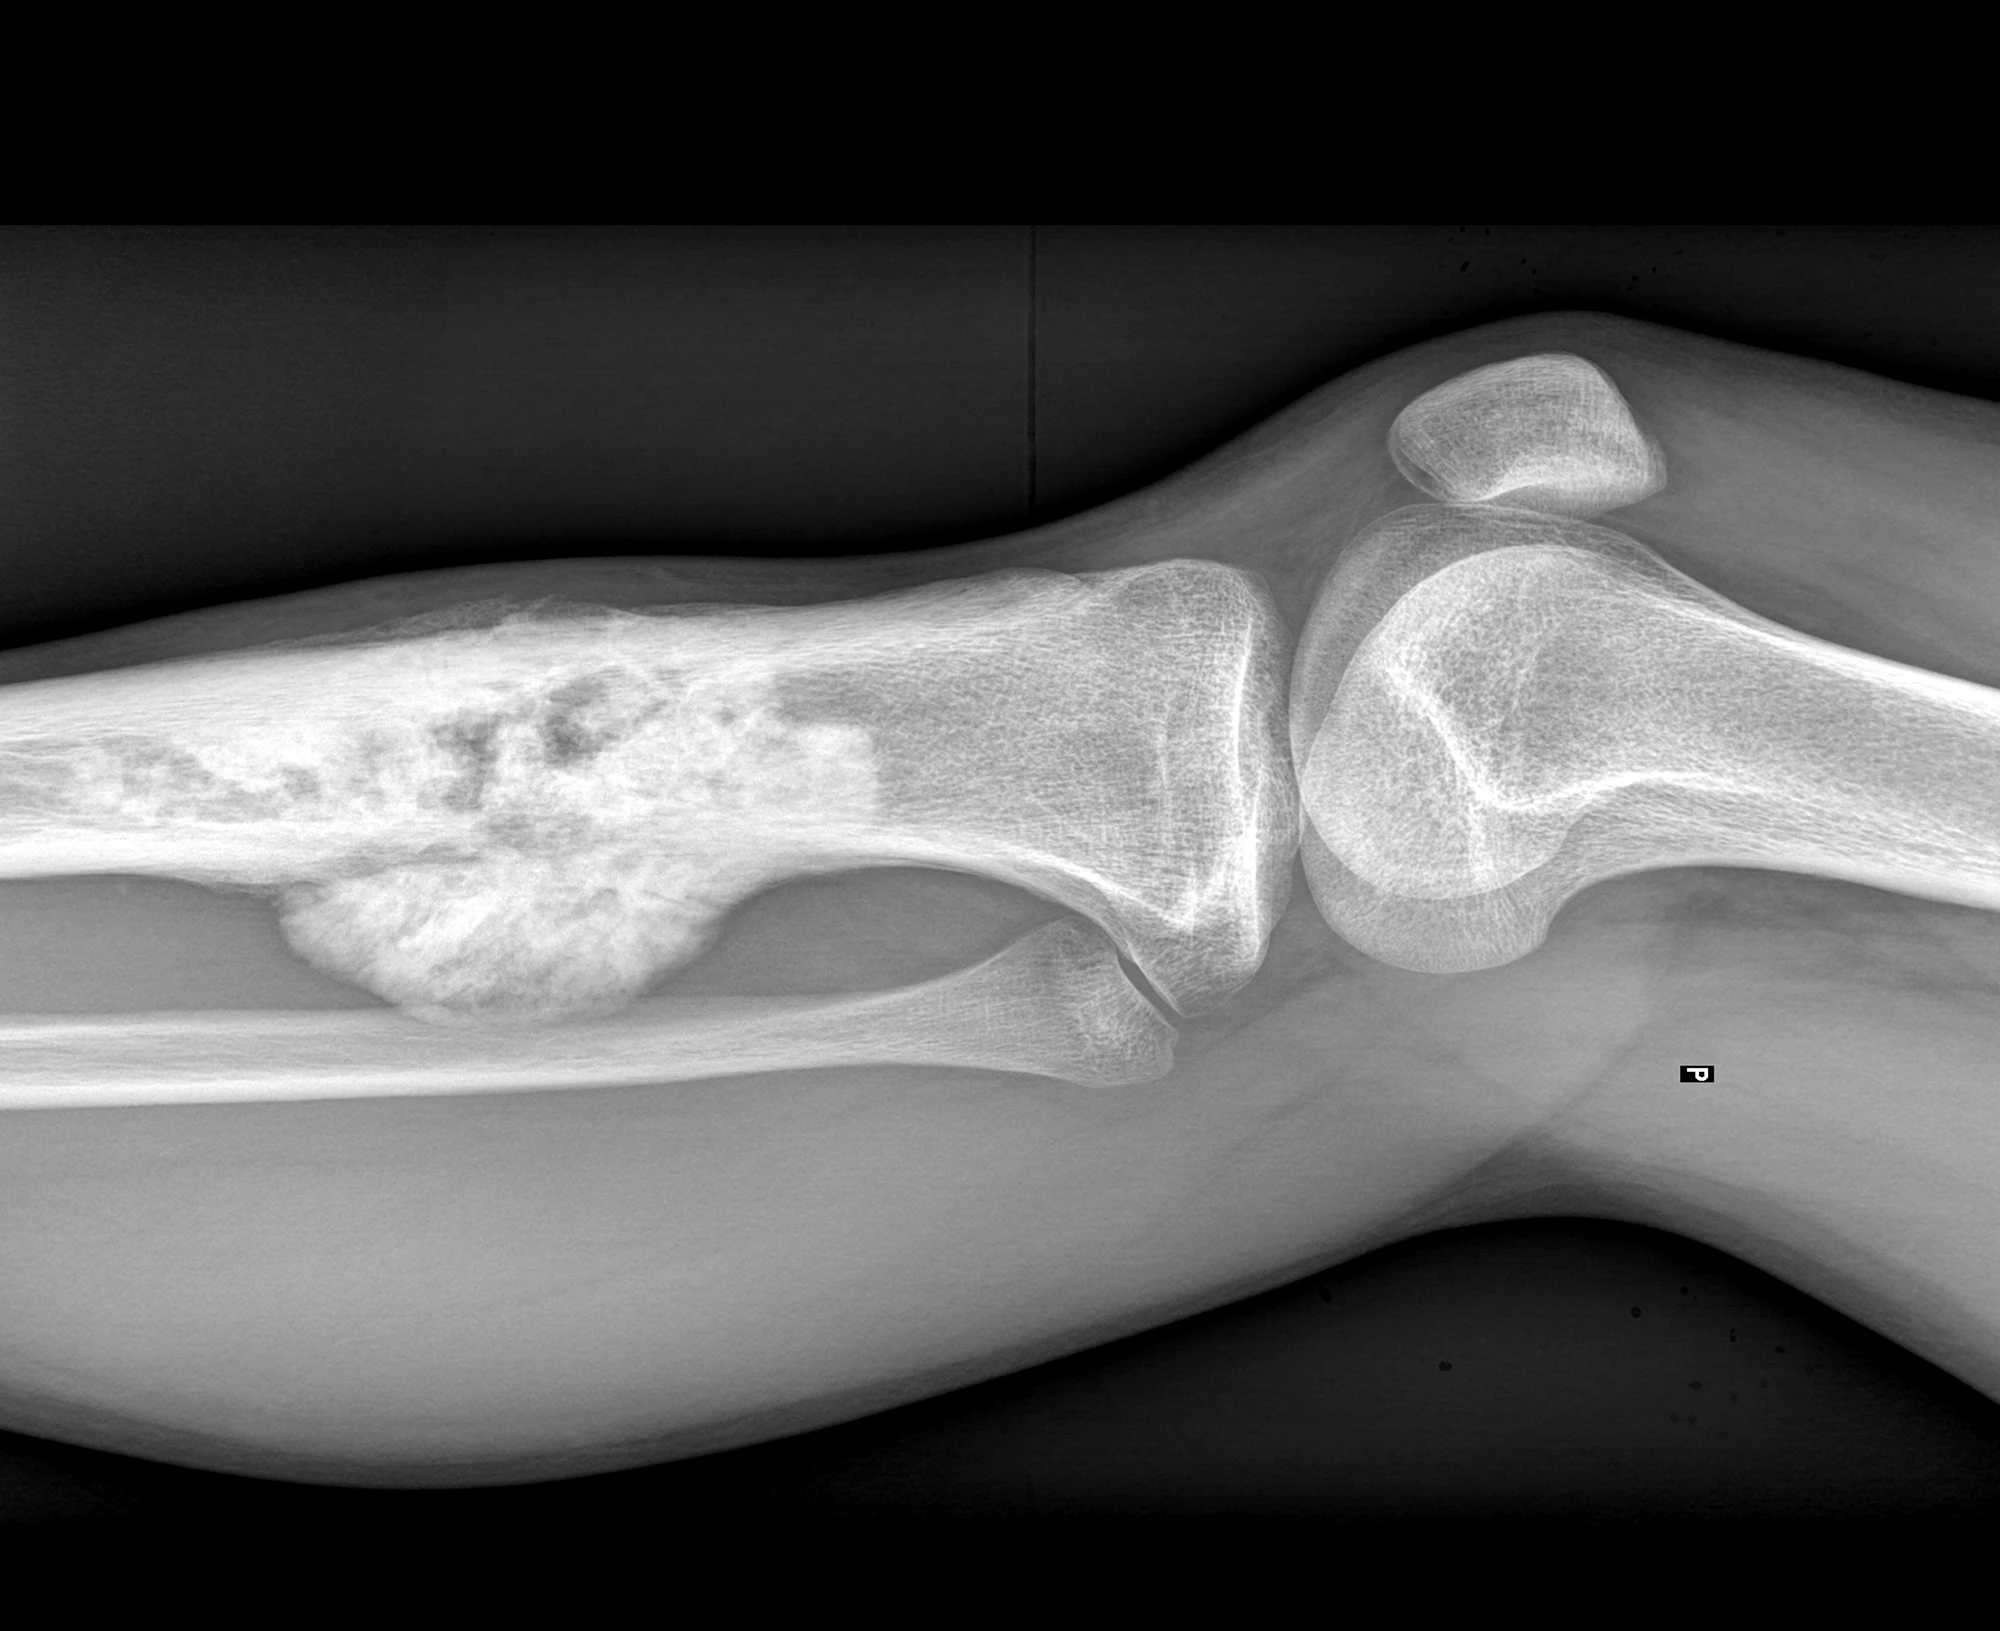

While osteosarcoma can appear in any bone in a dog’s body, it most commonly appears in the weight-bearing bones of the limbs. It’s aggressive and malignant and often metastasizes (spreads) to the lungs. Tumor resection, including limb amputation, is the usual first-line treatment, while chemotherapy is given in combination with surgery to improve survival time by reducing the risk of metastasis. OS Therapies’ recent clinical trial of OST-HER2 in dogs with limb osteosarcoma, published in Molecular Therapy, showed that the treatment prevented or delayed amputation, slowed tumor growth and metastasis, and improved survival. The results suggest that OST-HER2 is a less invasive and more targeted approach to treating this aggressive cancer.